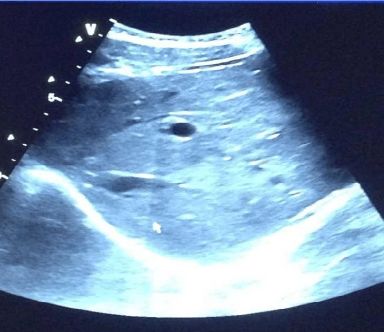

VE9在使用4C探头做腹部扫查的时候偶发性的出现由上至下的左右两面亮度不一样的一道分界线。

故障如图(二):

(图二)

故障分析与处理:

根据故障描述,这种情况属于偶发性故障,且在特定的检查部位出现。当更换扫查部位故障现象消失,因此可以排除硬件故障。分析应该是软件或者应用条件设置问题。